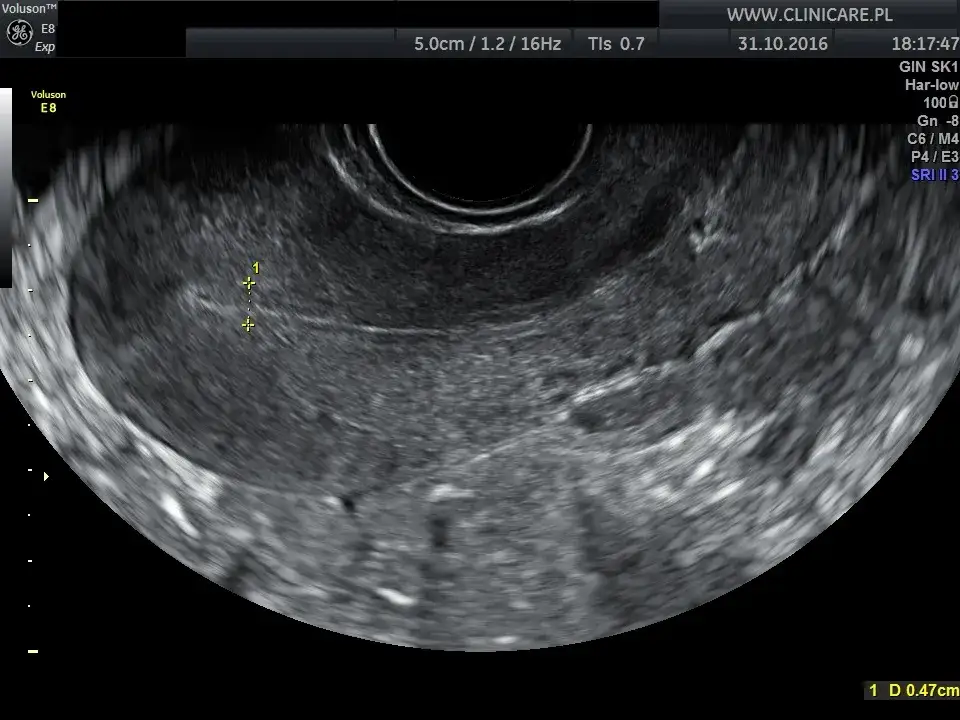

USG dopochwowe (transwaginalne): złoty standard w diagnostyce

USG transwaginalne, czyli dopochwowe, jest najczęściej wykonywanym i jednocześnie najbardziej dokładnym badaniem ultrasonograficznym w ginekologii. Dzięki specjalnej głowicy wprowadzanej do pochwy, mogę bardzo precyzyjnie ocenić macicę, grubość endometrium (błony śluzowej macicy), jajniki oraz jajowody. Pozwala to na wykrycie torbieli, mięśniaków, polipów czy innych zmian w obrębie tych narządów.